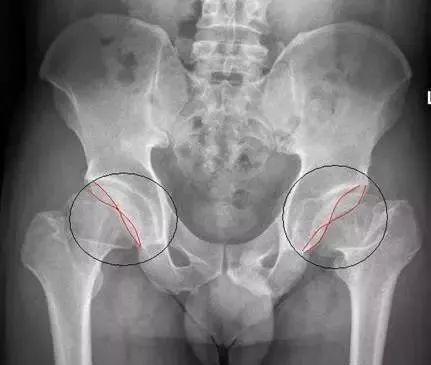

1、“交叉征”与髋关节撞击

在骨盆正位片上,髋臼前后缘线无交叉或在近端三分之一交叉,当髋臼后倾时,髋臼前后缘线出现交叉征象,即“交叉征”,此时容易发生髋臼与股骨头颈的撞击。常见于存在髋关节盂唇增生、髋关节置换前倾角不足的患者,怀疑此征时还应积极行其他影像学检查。